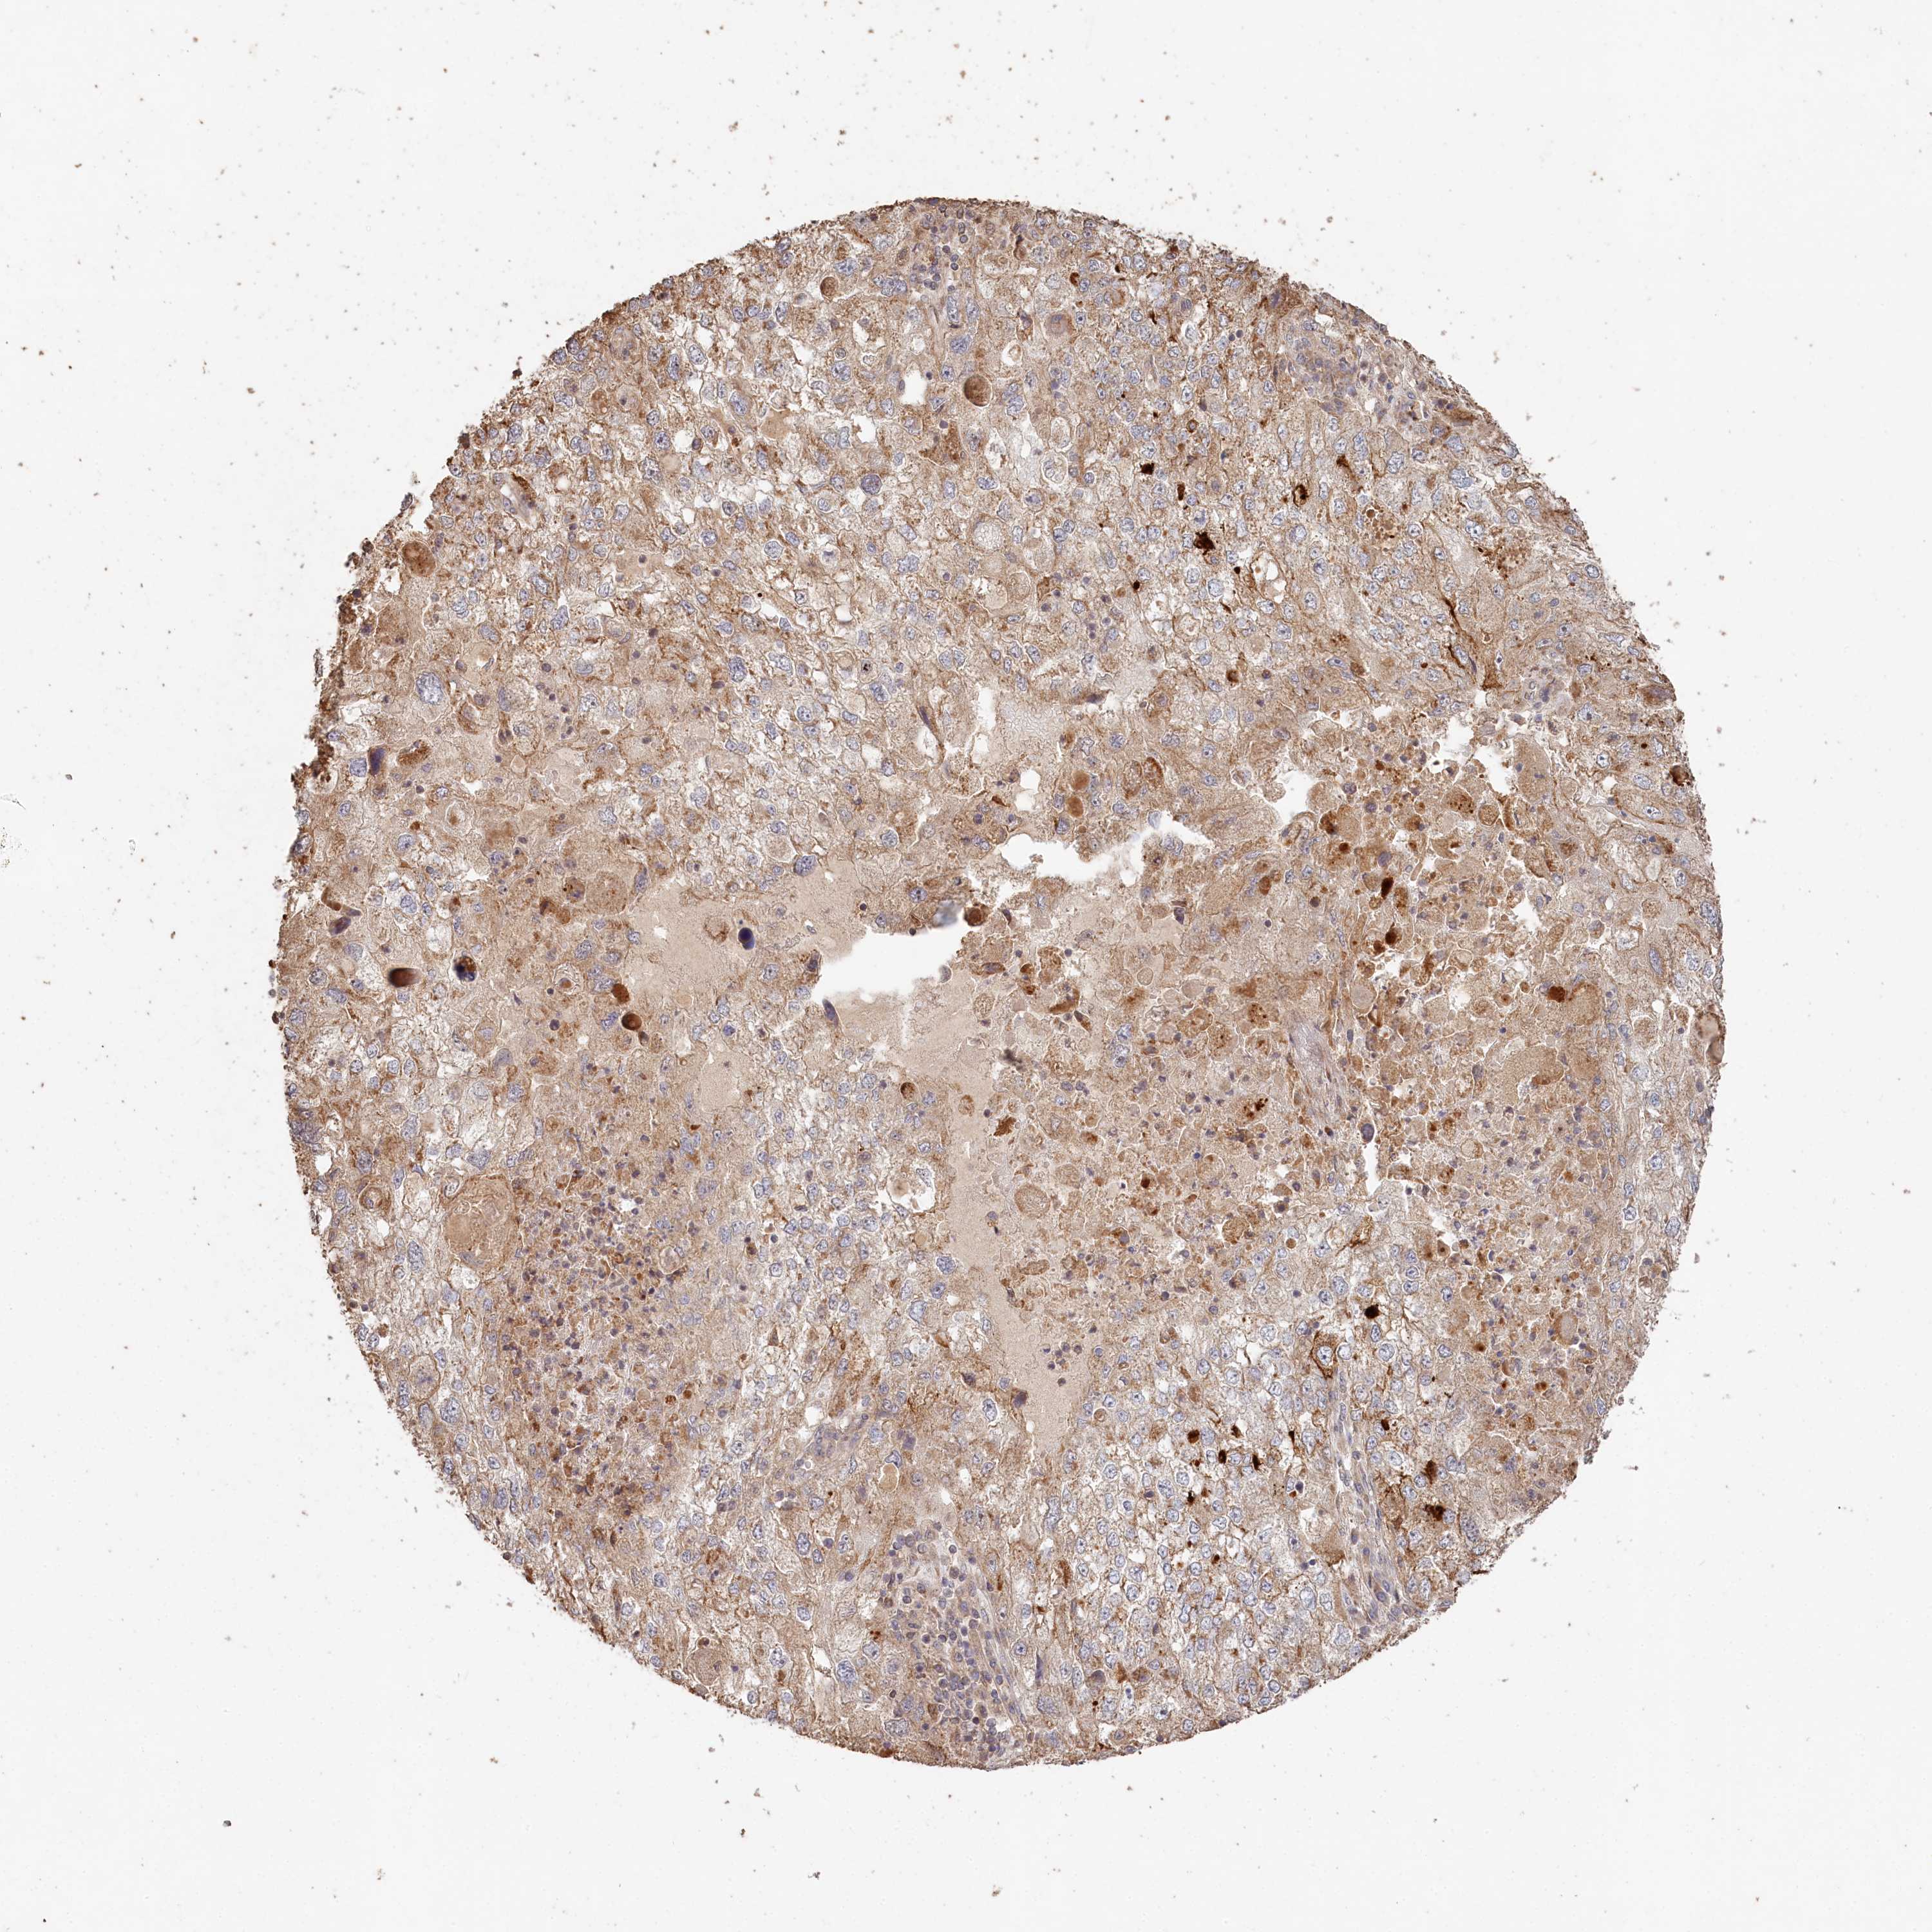

ENDOMETRIAL CANCER - Protein expressioni

A mouse-over function shows sample information and annotation data. Click on an image to view it in a full screen mode. Samples can be filtered based on level of antibody staining by selecting one or several of the following categories: high, medium, low and not detected. The assay and annotation is described here.

Note that samples used for immunohistochemistry by the Human Protein Atlas do not correspond to samples in the TCGA dataset.

Antibody stainingi

Antibody staining in the annotated cell types in the current human tissue is reported as not detected, low, medium, or high, based on conventional immunohistochemistry profiling in selected tissues. This score is based on the combination of the staining intensity and fraction of stained cells.

Each image is clickable and will lead to virtual microscopy that enables deeper exploration of all samples and also displays staining intensity scores, fraction scores and subcellular localization as well as patient and tissue information for each sample.

Antibody HPA038547

Antibody HPA038548

Staining

High

Medium

Low

Not detected

Intensity

Strong

Moderate

Weak

Negative

Quantity

>75%

75%-25%

<25%

None

Location

Nuclear

Cytoplasmic/membranous

Cytoplasmic/membranous,nuclear

Adenocarcinoma, NOS

Adenocarcinoma, metastatic, NOS